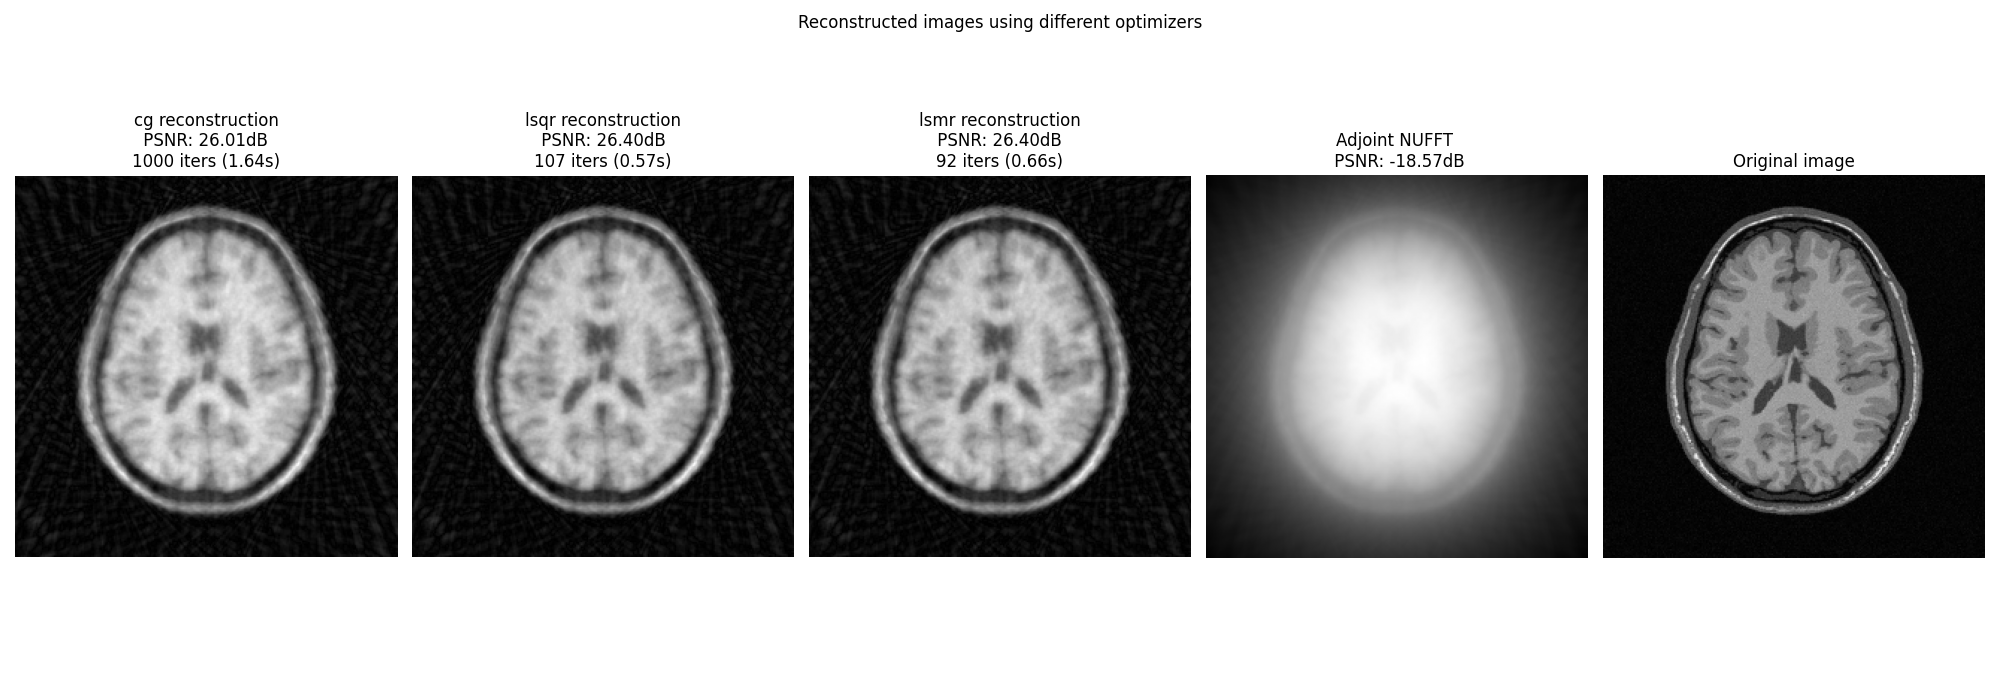

Using a damping regularization term#

The least-square problem can be regularized using a damping term to improve the conditioning of the problem. This is done by solving the following optimization problem:

# \min_x \|Ax - b\|_2^2 + \gamma \|x\|_2^2

Display images#

fig, axs = plt.subplots(1, len(OPTIM) + 2, figsize=(20, 7))

for i, optim in enumerate(OPTIM):

axs[i].imshow(abs(images[optim]), cmap="gray", origin="lower")

axs[i].axis("off")

axs[i].set_title(

f"{optim} reconstruction\n PSNR: {iterations_cb[optim]['psnr'][-1]:.2f}dB \n"

f"{len(iterations_cb[optim]['time'])} iters ({iterations_cb[optim]['time'][-1]:.2f}s)"

)

axs[-1].imshow(abs(ground_truth), cmap="gray", origin="lower")

axs[-1].axis("off")

axs[-1].set_title("Original image")

axs[-2].imshow(

abs(adjoint),

cmap="gray",

origin="lower",

axs[-2].axis("off")

axs[-2].set_title(

f"Adjoint NUFFT \n PSNR: {psnr(abs(adjoint), abs(ground_truth), data_range=ground_truth.max()):.2f}dB"

fig.suptitle("Reconstructed images using different optimizers")

fig.tight_layout()

plt.show()